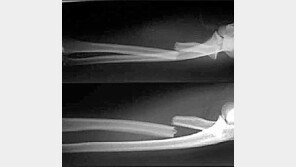

카타르전에서 부상을 당한 손흥민(25·토트넘·사진)이 결국 수술대에 오르게 됐다. 의료계 관계자들은 손흥민의 부상이 예상과 달리 장기화할 수 있다고 분석하고 있다. 소속팀은 물론이고 대표팀 전력에도 큰 여파를 미칠 것으로 전망된다. 의료계 관계자에 따르면 손흥민은 16일 서울 경…